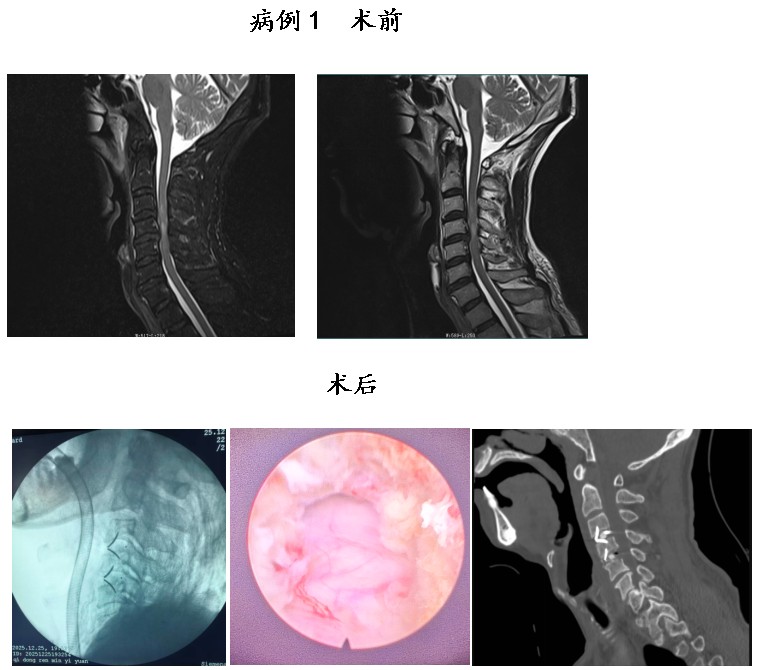

通訊員鐘嵐報道:近期,衡陽市中心醫(yī)院駐祁東縣人民醫(yī)院脊柱外科副主任醫(yī)師申寬宏團隊再創(chuàng)診療佳績,成功為2名頸脊髓損傷患者實施內(nèi)鏡輔助下頸椎前路減壓融合內(nèi)固定術(shù),實現(xiàn)術(shù)中脊髓零侵襲,術(shù)后患者神經(jīng)功能恢復(fù)良好、疼痛癥狀顯著緩解,贏得患者及家屬的高度認可,在區(qū)域內(nèi)樹立了良好的醫(yī)療口碑,取得了顯著的社會效益。

接診后,申寬宏團隊在高清視野下高效完成椎間盤或髓核摘除、椎管精準(zhǔn)減壓等核心操作,徹底解除脊髓與神經(jīng)的壓迫癥狀;同時,精準(zhǔn)植入融合器與內(nèi)固定裝置,實現(xiàn)病變椎體的牢固穩(wěn)定與骨性融合,有效重建脊柱正常生理曲度與力學(xué)平衡。

申寬宏介紹,該術(shù)式相較傳統(tǒng)開放手術(shù),具有創(chuàng)傷小、出血少、術(shù)后疼痛輕、恢復(fù)快等顯著優(yōu)勢,在保障治療效果的同時,大幅縮短了患者的住院時間,降低了術(shù)后并發(fā)癥發(fā)生風(fēng)險,為頸脊髓損傷患者的快速康復(fù)奠定了堅實基礎(chǔ)。